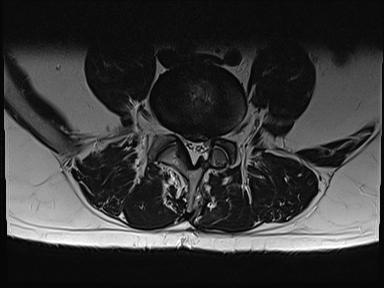

Ich werde mal 2 Bilder der MRT Untersuchung hochladen.

Heutiges MRT ergab das die Bandscheibe immer noch soweit raus ist wie vor 2 Monaten. Also ist nicht weiter gerutscht. Das Narbengewebe ist nur noch schwach auf Kontrasmittel ansprechbar was bedeutet das der Heilungsprozess noch nicht abgeschlossen ist. Einen richtigen berricht bekomme ich erst am montag leider.

Die Ncs können sich nicht ganz erklären wieso es so ist bei mir aber dad die bamdscheibe schon ganzschön raus ist aber noch genug liquorwasser da ist das die cauda Fasern frei schwimmen.

Narbengewebe ist da und umschließt den dura Sack was dazu führt das de4 nerven Strang nicht ausweichen kann....